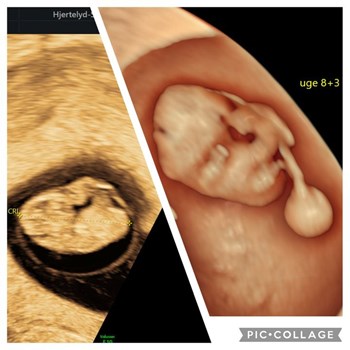

Se hele opslaget på HERNING SVØMMEHALs FacebooksideBilleder fra livets begyndelse ✨ Scanning i 9. graviditetsuge. Billede i 2D og 3D. Læg mærke til de bittesmå arme og ben. Simpelthen fantastisk 🤩 Book en tidlig scanning, for at få svar på de første...

Se hele opslaget på Hjertelyd - scanningsklinik for gravides Facebookside